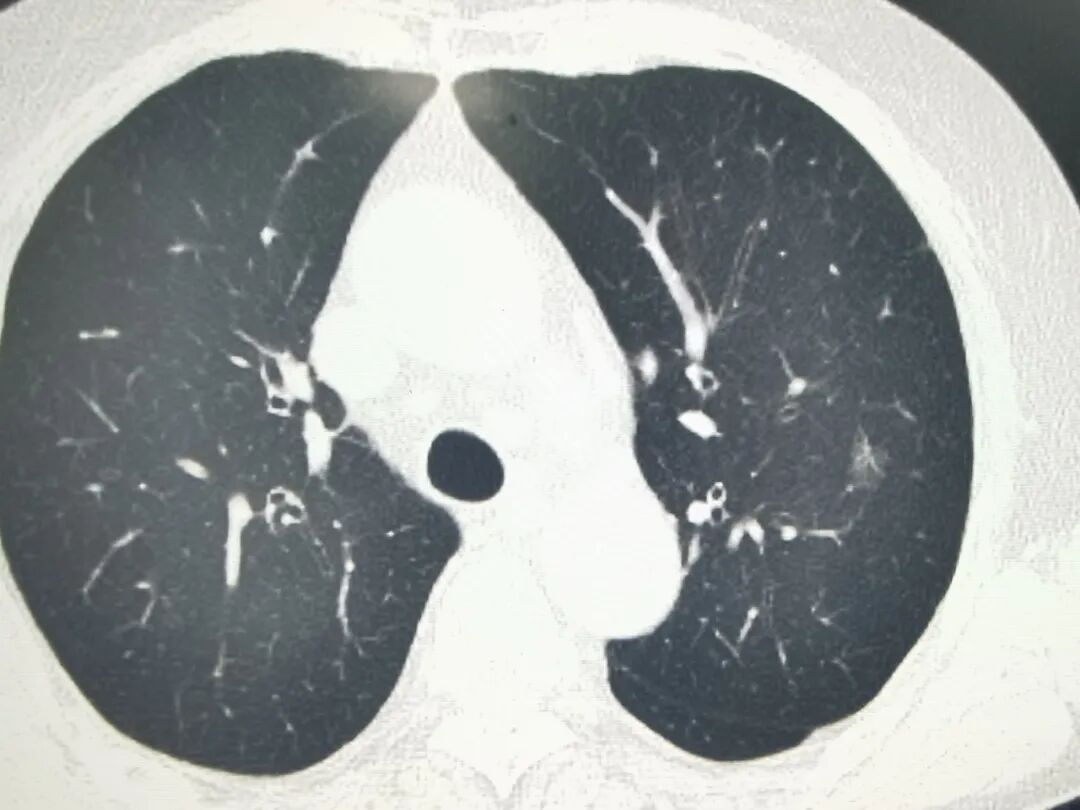

▲图片仅参考,非本文病例